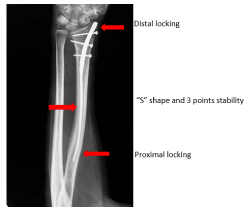

Figure 3. The reduction of the fracture opens the compaction chamber which collapse is opposed by the elastic reaction of the nail. The self-stability is ensured by an "S" design with 3 fix points

The radius fracture is reduced by manual traction. The nail is inserted at the level of the snuffbox, outside the tendinous areas. The entrance is perforated with a small square point. The nail has an "S" shape. It is inserted with curvature upside down to fit the metaphyseal angle, it is then turned over and entirely inserted. It is stopped by the aiming frame which stumbles on the radial styloid. Locking is performed as for the femur or tibia. The nail is freestanding thanks to its "S" design and its 3 points of support. It is also elastic since the 2/3 of the nail are fine as a pin (2 mm) and automatically realigns the distal epiphysis and keeps the focus open. It must be locked at its. distal part, with at least two epiphyseal screws (Figure 7).

Figure 7. Radiological aspects of the reduction and nailing of a distal radius fracture